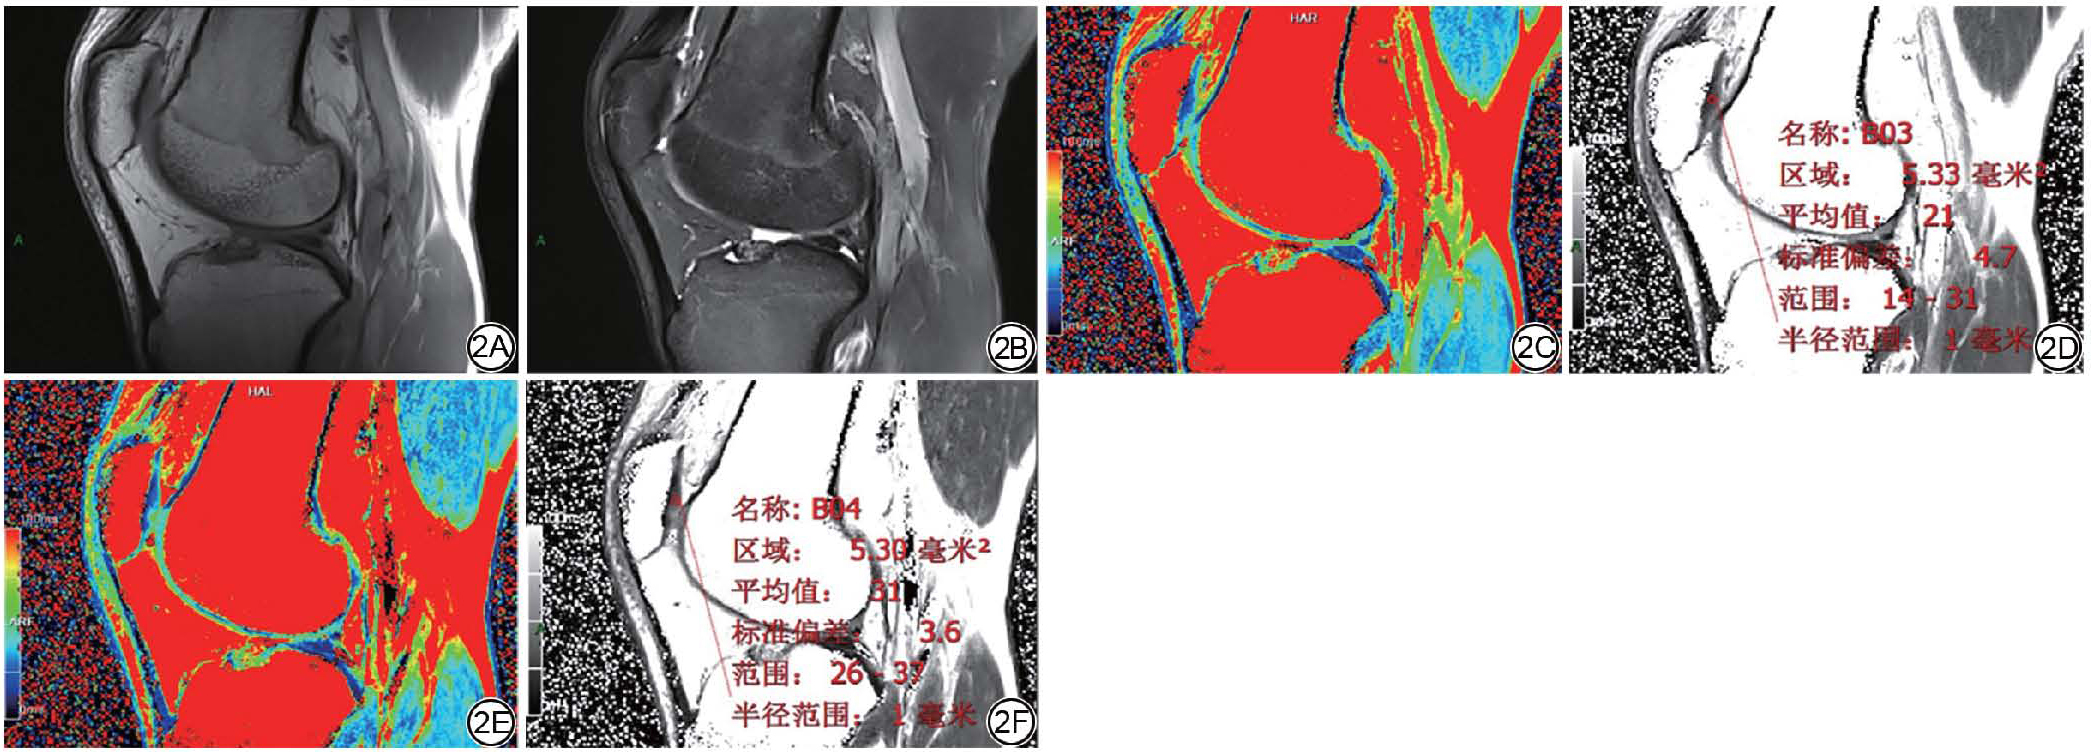

对所有受试者膝关节MRI图像进行PFJ PC Recht分级,共分为4组:Recht 0~Ⅰ级、Recht Ⅱ级、Recht Ⅲ级、Recht Ⅳ级。由其中1名高年资副主任医师应用西门子工作站软件在膝关节矢状位T2 mapping伪彩图相对应的原始图像中勾画PC、内侧半月板(medial meniscus, MM)、外侧半月板(meniscus lateralis, ML)、前交叉韧带(anterior cruciate ligament, ACL)、后交叉韧带(posterior cruciate ligament, PCL)、腘肌(popliteus muscle, PM)、内侧腓肠肌(medial gastrocnemius, MG)感兴趣区(region of interest, ROI)并测量T2值。T2值测量分别于半程马拉松运动前及运动后进行,两次测量尽可能选取膝关节同一解剖层面。由同一观察者在同一幅图像上对ROI连续勾画3次,取3次测量结果的平均值作为最终T2值。其中,PC的ROI定位在正中矢状位层面,采用直径3~5 mm的圆形区域;勾画时需避开相邻组织结构,以提高T2值测量的精准度(图2)。

图2  男,39 岁,髌股关节髌软骨显示及ROI 勾画示意图。2A:T1WI 矢状位序列;2B:FS-T2WI 矢状位;2C:半程马拉松前T2 mapping 序列伪彩图;2D:图2C相同层面矢状位原始图测量ROI T2 值,T2 值为21 ms;2E:半程马拉松后图2C相近层面T2 mapping 序列伪彩图;2F:图2E 相同层面矢状位原始图测量ROI T2 值,T2 值为31 ms。ROI:感兴趣区;FS:脂肪抑制。

Fig. 2  A 39-year-old male, schematic diagram of patellar cartilage display and ROI delineation. 2A: T1WI sagittal sequence; 2B: FS-T2WI sagittal sequence; 2C: Pre-half marathon, T2 mapping sequence pseudocolor image; 2D: ROI T2 value measurement on the sagittal original image corresponding to Figure 2C, showing a T2 value of 21 ms; 2E: Post-half marathon, T2 mapping sequence pseudocolor image of a similar sagittal plane to Figure 2C; 2F: ROI T2 value measurement on the sagittal original image corresponding to Figure 2E, showing a T2 value of 31 ms. ROI: region of interest; FS: fat suppression.